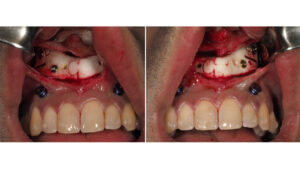

مراحل برش دهانی در عمل جراحی فک

ممکن است بپرسید اگر پوست باز نمیشود پس ما چگونه این ابزارهای دقیق را به استخوان میرسانیم و آن را برش میدهیم؟

دهلیز دهانی همان فضای بین لبها و دندانهاست که وقتی لپ خود را باد میکنید متوجه آن میشوید. ما برشهایی را در عمق این ناحیه روی بافت مخاطی لثه ایجاد میکنیم، این بافت ویژگیهای منحصر به فردی دارد که پوست صورت فاقد آن است.

برش فک بالا

برای دسترسی به فک بالا ما از برشی استفاده میکنیم که به آن برش حاشیه لثهای یا وستیبولار فک بالا میگوییم. این برش دقیقا در بالای ریشه دندانهای فک بالا و زیر لب بالا ایجاد میشود. اگر برش خیلی پایین باشد ممکن است به لثه متصل به دندانها آسیب بزند و باعث تحلیل لثه شود و اگر خیلی بالا باشد ممکن است وارد فضای عضلات گونه شود.

بعد از ایجاد این برش بافت نرم را کنار میزنیم و به تمام قسمتهای استخوان فک بالا دسترسی پیدا میکنیم. نکته جالب اینجاست که چون برش افقی است و در راستای خطوط طبیعی کشش بافت دهان قرار دارد فشار کمی روی بخیهها وارد میشود و جوش خوردن آن بسیار سریع است.

مسیر برش و دسترسی به فک پایین

دسترسی به فک پایین کمی سختتر است زیرا عصب حسی لب پایین از داخل استخوان این ناحیه عبور میکند. برش در اینجا معمولا در قسمت انتهایی فک و در کنار دندانهای آسیاب بزرگ ایجاد میشود.

این برش به سمت بالا و روی لبه جلویی شاخه صعودی فک پایین امتداد مییابد. شاید تصور کنید چون فک پایین متحرک است این برش موقع صحبت کردن اذیتکننده باشد اما محل آن به گونهای انتخاب میشود که کمترین اصطکاک را با غذا خوردن یا صحبت کردن داشته باشد.

در این ناحیه بافت ضخیمتری داریم و عضلات قوی جونده به استخوان متصل هستند. هنر جراحی در اینجا این است که برش را طوری ایجاد کنیم که هنگام جدا کردن عضلات برای رسیدن به استخوان کمترین خونریزی ایجاد شود و بعد از عمل هم عضلات بتوانند دقیقا سر جای خودشان جوش بخورند تا فرم صورت تغییر نکند.